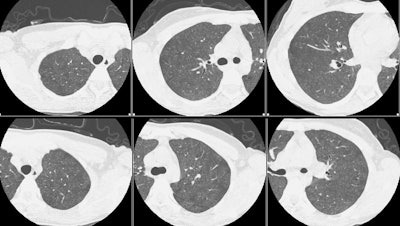

Her CT scan demonstrated diffuse, poorly defined centrilobular nodular areas of ground glass opacification. (Click CT to magnify)